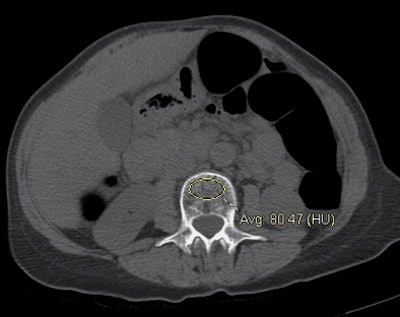

| CT data from virtual colonoscopy exam shows individual with normal BMD (top) and another with osteoporosis (bottom). Both cases were assessed at the L3 level using the simple ROI method, with results confirmed by DEXA. Images courtesy of Perry Pickhardt, MD. |

"We simply lay an ovoid ROI and measure the mean attenuation in Hounsfield units," he said. Reconstructions were performed at both 1.5-mm and 5-mm thicknesses and the two were compared -- but the focus was on 5-mm thicknesses because they are compatible with any routine CT study.

For example, at the L3 level, a trabecular attenuation threshold of 130 HU was 100% sensitive for osteoporosis (29/29); 61 (72.6%) of 84 adults with normal BMD were above the 130 HU threshold, while 108 (82.4%) of 131 below 130 HU had osteopenia or osteoporosis at DEXA. Similar results were found for other T12-L5 levels; complete results are shown below.